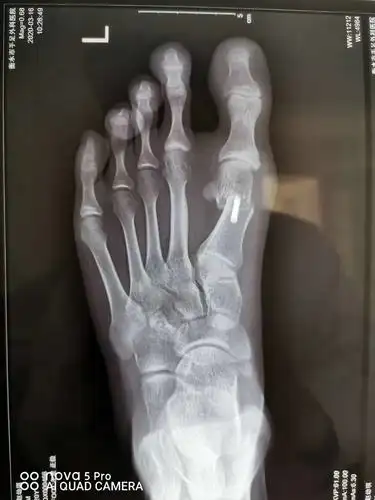

负重x线片观察:第一二跖骨间夹角增大明显,第二跖趾关节半脱位.